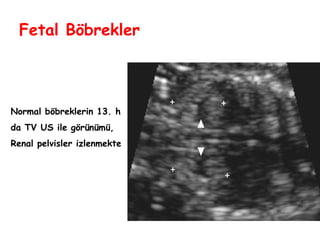

Fetal Böbrekler

Normal böbreklerin 13. h

da TV US ile görünümü,

Renal pelvisler izlenmekte